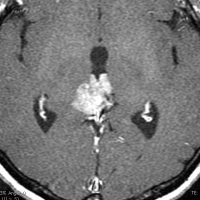

40代男性のPPTIDグレード3です。早朝の激しい頭痛で発症しました。morning headacheは松果体腫瘍の特徴でもあります。これに対して内視鏡による第3脳室開窓術と生検術がなされてから紹介されてきました。生検術前のHCG-beta 2.1mIUと陽性でしたからgerminomaを強く疑いましたが,生検病理診断はrosette構造があり中等度の核異型を有するPPTIDであり,MIB-1 8%でした。短期間の間に増大していました。グレード3 PPTIDと判断されます。

第3脳室開窓後のCTです。左のCTでは小さな石灰化がみられます。右の造影CTでは小さなのう胞部分をのぞいて均一な増強効果がみられます。

MRIガドリニウム増強像です。腫瘍境界がわりにはっきりしていて,中脳や視床に浸潤像がありませんから,松果体芽腫ではないことが解ります。でも,この画像だけからは,松果体細胞腫やジャーミノーマとの区別はつきません。

PPTIDであり,MIB-1が比較的高いので,脳脊髄照射 24グレイ・12分割と腫瘍局所照射30グレイ・15分割の放射線治療をしましたが,腫瘍はあまり縮小しませんでした。その後に,後頭開頭経テント法で腫瘍を全摘出しました。さらに術後にテモダール6コースを加えました(テモダールが有効である根拠はありません)。記載時点では患者さんは元気で復職していて,残存腫瘍もなく,眼球運動障害などの神経症状も全くありません。